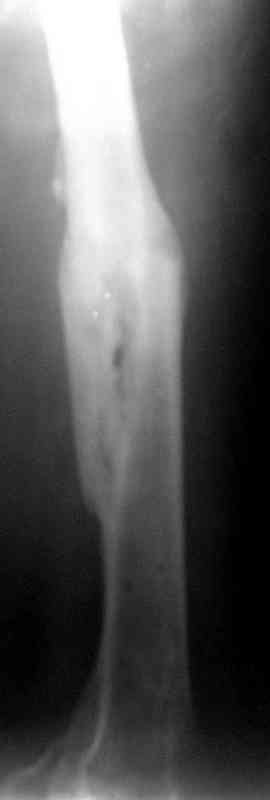

Больной А., 28 лет, поступил в НИИ им. Н.В. Склифосовского 22.12.99 после падения на улице. Жалобы на боли в области левого тазобедренного сустава и левом бедре. Из анамнеза следовало, что 20.06 во время прыжка с парашютом у него возник закрытый оскольчатый перелом средней трети левой бедренной кости со смещением отломков, по поводу чего в одной из ЦРБ Московской области через 3 дня после травмы был произведен открытый интрамедуллярный остеосинтез штифтом типа Кюнчера.

Послеоперационное течение было гладким. Больной ходил при помощи костылей с дозированной нагрузкой на оперированную конечность.При осмотре в НИИ им. Н.В. Склифосовского через 6 месяцев после травмы:

левое бедро и левый коленный сустав несколько увеличены в объеме, отечны, пальпаторно определяется болезненность в средней трети бедра;

по его наружной поверхности послеоперационный рубец - рана зажила первичным натяжением. При измерении длины бедер обнаружено укорочение левого бедра на 4,5 см. На рентгенограммах этого бедра: ось конечности правильная, отмечается захождение основных костных фрагментов по длине, проксимальный конец штифта выступает слишком медиально и высоко относительно большого вертела, периостальная мозоль незначительна.22.12 - через 6 месяцев после операции, произведенной в ЦРБ, нами по поводу замедленно консолидирующего перелома левой бедренной кости с ее абсолютным укорочением под наркозом произведена операция: удаление штифта, закрытый блокирующий интрамедуллярный остеосинтез перелома левого бедра штифтом без рассверливания (UFN) длиной 40 см, диаметром 10 мм с блокированием только проксимальных отверстий (динамический остеосинтез). Наложен аппарат Илизарова на 4 полукольцах с целью удлинения укороченного бедра. Послеоперационное течение без особенностей. Ежедневно осуществляли дистракцию отломков на 1 мм. Через 3 недели после операции больной выпи-сан на амбулаторное лечение с продолжением дистракции отломков. В течение 1,5